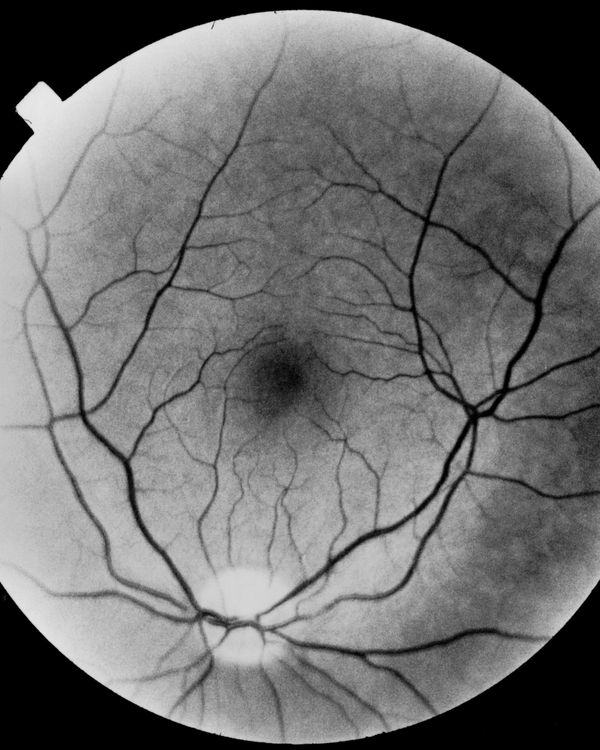

It’s surprising how often memories appear to us in visual form, similar to snapshots in the psyche that only the time can erase.

After all, after careful reflection, sight is not only the product of the activity of our eyes, it is also and above all the gaze of our mind through memory.

Hence, starting from this contradiction only apparently irresolvable, the search for a visual narration of the fear of losing sight is closely linked to memory, although the sight ceases, what remains is the entirety of the experiences that time offers us to the extent that we exist and existence is nothing more than a continuous encounter between us, the world and what goes beyond us.